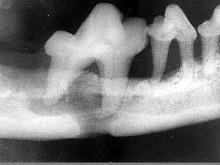

问题 颌面外伤患者,咬合错乱,下唇麻木张口受限,经X 线检查如图。应该为 ( )

选项 A.上颌骨骨折 B.颧弓骨折 C.牙槽突骨折 D.下颌骨骨折 E.颧骨骨折

答案 D